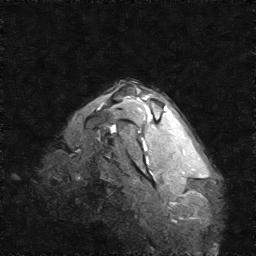

| Numero della serie: | 7 | Descrizione della serie: | STIR TI 80 SAG |